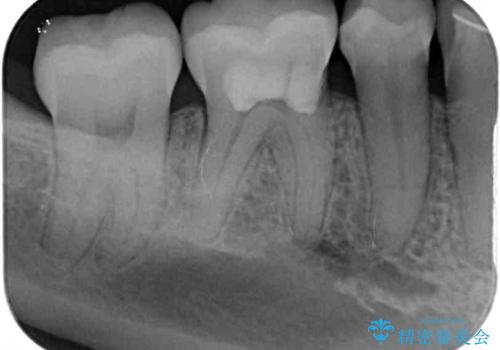

矯正治療後には、下顎臼歯の目立つ銀歯をセラミックインレーにて修復治療を行いました。

口を開けたときに金属が見えなくなり、患者様には大変満足していただきました。